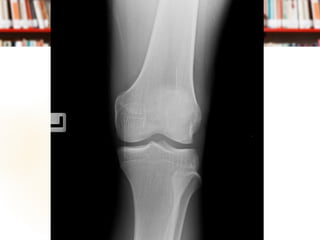

 Film Knee AP, Lateral

Management at ER Film Knee AP, Lateral